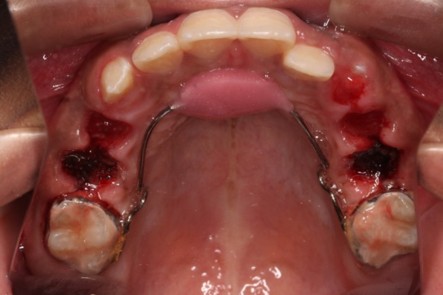

- Pulpotomy, pulpectomy

- Interceptive or habit breaking orthodontics to minimize teeth and jaw irregularities.